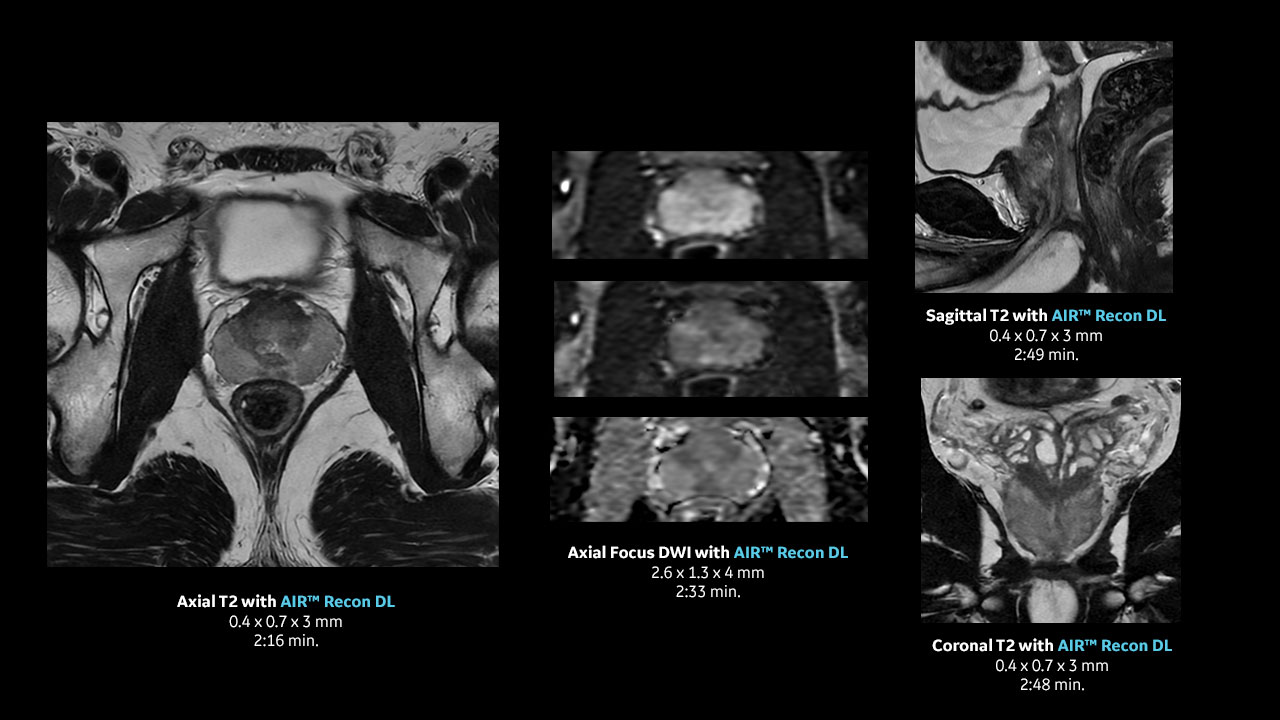

With access to the latest advanced AI technology, you can scan all anatomies and achieve pin-sharp images. Our pioneering Deep Learning-based reconstruction algorithm AIR™ Recon DL accelerates scan time and puts patients at ease.